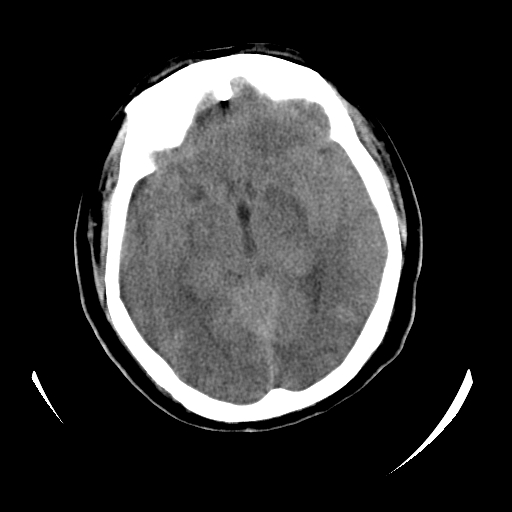

女,53岁,发现昏迷1天,血压不高,有精神病史。临床诊断:脑梗死?

ct诊断:1、双侧基底节区对称性脑梗塞。

2、双侧额叶、枕叶广泛密度减低,考虑缺血梗塞可能性大。

3、脑池小,脑沟浅,提示颅内高压。

测左枕叶白质ct值 约22hu 。请各位老师给出恬当诊断。

征象:病变呈对称性分布于双侧大脑半球,累及范围广泛,白质较灰质密度减低更为明显;脑沟变浅,脑池变窄;

支持3楼老师的分析,颅内广泛性 对称性低密度改变,特别是双侧基底节区的病灶,首先应考虑:缺氧性脑梗死。

考虑 中毒性脑病,脑肿胀。病因待定,结合临床仔细了解病史

长期的服用神经抑制药物,考虑药物中毒引起的脑改变。